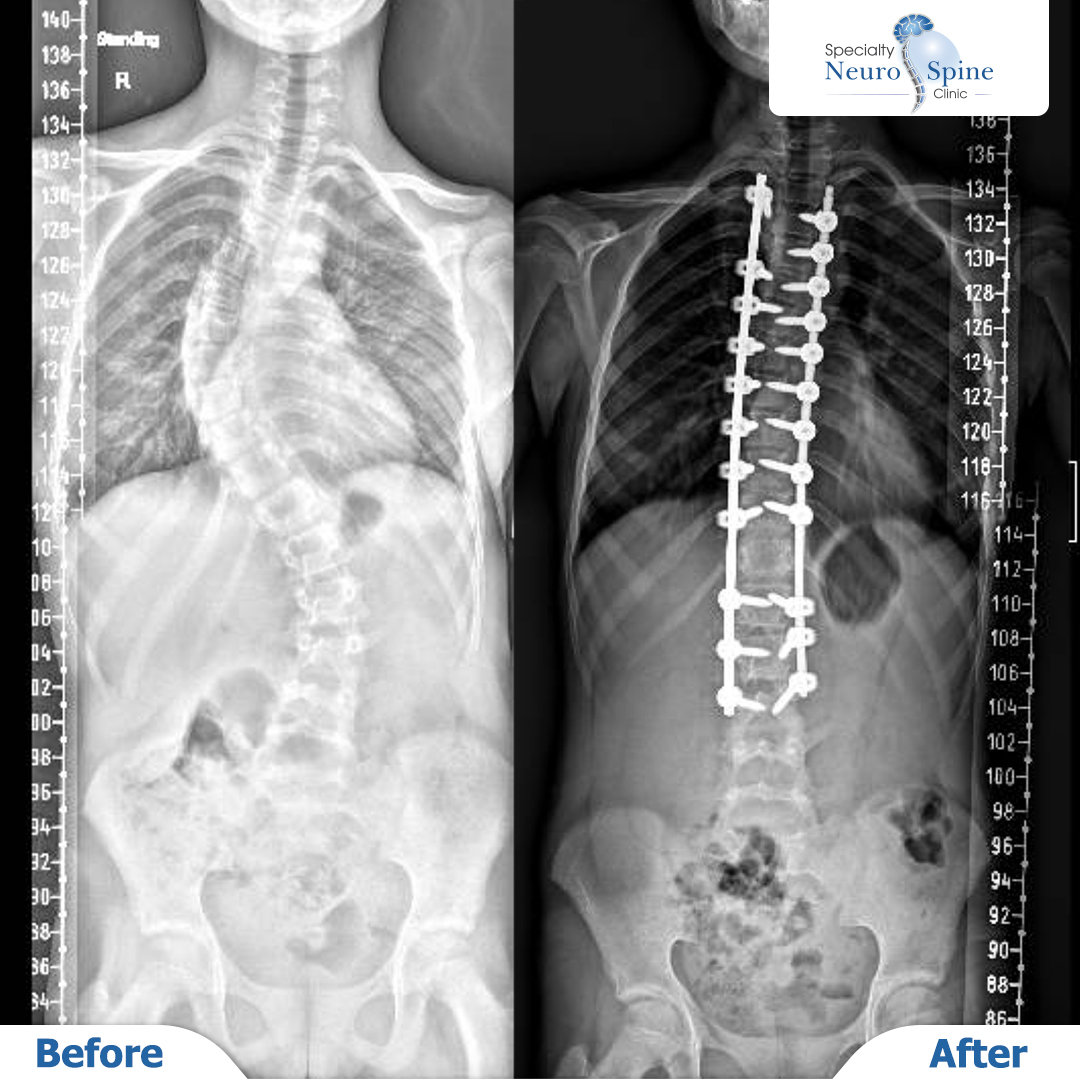

بيلسان (12 عامًا): تصحيح انحراف العمود الفقري باستخدام التدخل الجراحي المحدود

قبل وبعد صور الأشعة لمريضتنا الغالية بيلسان، البالغة من العمر 12 عامًا،

أجرى لها الدكتور فراس الحسبان عملية جراحية لتصحيح انحراف العمود الفقري من الفقرة الصدرية الثالثة إلى القطنية الثالثة باستخدام التدخل الجراحي المحدود بالمنظار.